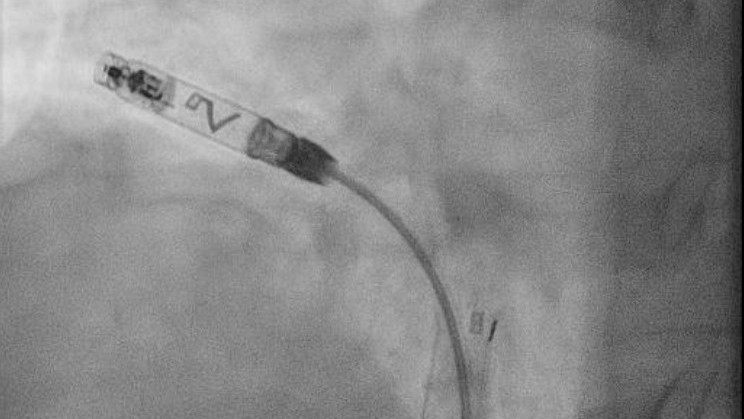

Bei einer schweren Lungenembolie ist schnelles Handeln entscheidend, um das Herz zu entlasten. Wenn Medikamente allein nicht ausreichen oder das Blutungsrisiko für eine systemische Lyse zu hoch ist, setzen wir moderne, kathetergestützte Verfahren ein, um die Lungengefäße mechanisch oder lokal-medikamentös zu befreien:

- Gezielte Applikation von Lyse-Medikamenten direkt in den Thrombus über spezielle Katheter.

- EKOS-Verfahren: Zusätzliche Nutzung von Ultraschallwellen zur Auflockerung des Gerinnsels für eine effizientere Wirkstoffaufnahme. Deutlich geringere Blutungsgefahr im Vergleich zur systemischen Infusion durch niedrigere Dosierung.